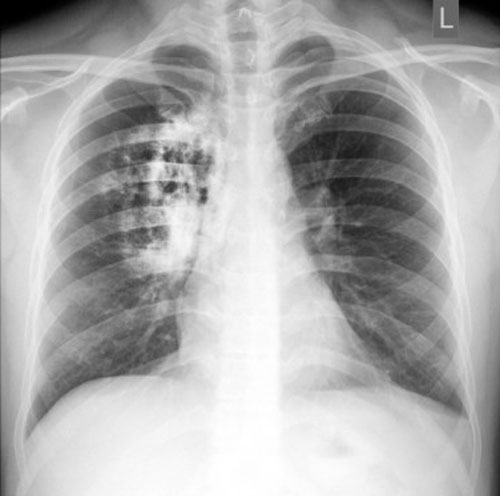

Ung thư phổi có thể gây ra t́nh trạng nhiễm trùng ảnh hưởng đến đường hô hấp và dẫn đến các bệnh như viêm phế quản hoặc các bệnh nhiễm trùng măn tính khác. Nếu bạn bị nhiễm trùng phổi măn tính, bạn nên dành thời gian đi chụp X-quang phổi để biết ḿnh có nguy cơ bị ung thư phổi hay không.

Click image for larger version

Name:	10-dau-hieu-canh-bao-som-benh-ung-thu-phoi-1081603.jpg